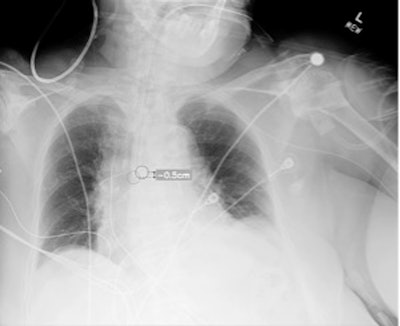

Plain chest radiograph showing overlay from Critical Care Suite, with segmentation of ETT, identification of tube tip and carina, and calculation of distance between them.Critical Care